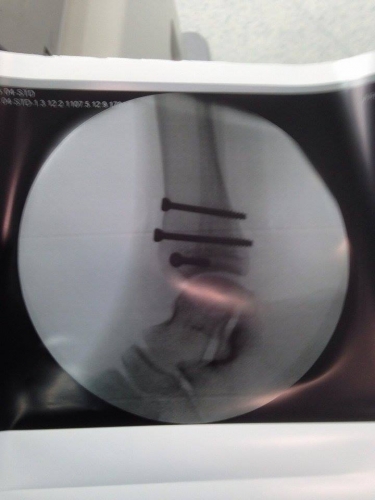

تعرض الطالب (ز٬ س) من مدرسة فراس العجلوني بعّمان للضرب المبرح من قبل احد المعلمين مما أدى الى تعرضه لكسر في كاحل إحدى قدميه.

وإثر الكسر تم اجراء عملية جراحية للطالب وزرعت براغي بقدمه.